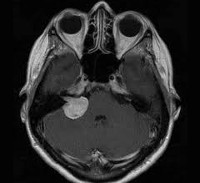

На T1-взвешенных МР-изображениях опухоль имеет пониженную или не отличающуюся от мозжечка плотность, при введении контрастного вещества контрастность опухоли значительно возрастает. На Т2-взвешенных изображениях опухоль, как правило, гиперинтенсивна.

МРТ головного мозга в случае невриномы выявляет на Т1-взвешенных снимках гипо- или изоинтенсивное, а на Т2-взвешенных – гиперинтенсивное образование. Для опухолей размером 3 и более см характерна гетерогенность сигнала, связанная с наличием в них кистозных участков. Возможна визуализация деформации ствола мозга и мозжечка. При проведении контрастной МР-томографии в 70% наблюдается гетерогенное накопление контраста.